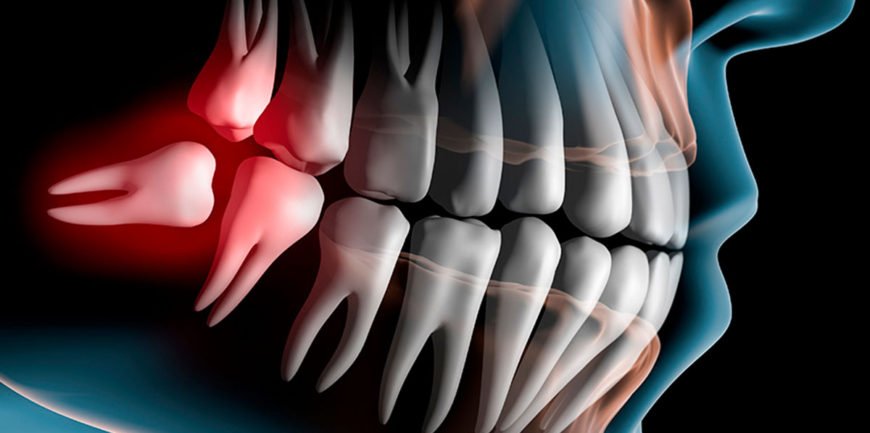

Chirurgia Estrattiva: Soluzioni per Ogni Caso

Il settore della Chirurgia Estrattiva si dedica alle estrazioni dentali, necessarie per fratture, carie, infezioni croniche o trattamenti ortodontici. Dental Equipe esegue ogni tipo di estrazione, dalla più semplice, come i denti decidui in fase di mobilità, alla forma più complessa di inclusione.